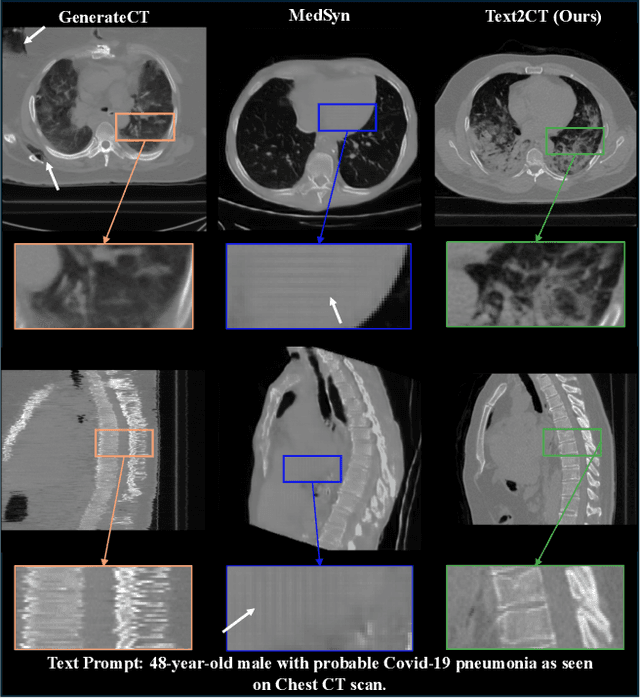

Abstract:Recent progress in vision-language modeling for 3D medical imaging has been fueled by large-scale computed tomography (CT) corpora with paired free-text reports, stronger architectures, and powerful pretrained models. This has enabled applications such as automated report generation and text-conditioned 3D image synthesis. Yet, current approaches struggle with high-resolution, long-sequence volumes: contrastive pretraining often yields vision encoders that are misaligned with clinical language, and slice-wise tokenization blurs fine anatomy, reducing diagnostic performance on downstream tasks. We introduce BTB3D (Better Tokens for Better 3D), a causal convolutional encoder-decoder that unifies 2D and 3D training and inference while producing compact, frequency-aware volumetric tokens. A three-stage training curriculum enables (i) local reconstruction, (ii) overlapping-window tiling, and (iii) long-context decoder refinement, during which the model learns from short slice excerpts yet generalizes to scans exceeding 300 slices without additional memory overhead. BTB3D sets a new state-of-the-art on two key tasks: it improves BLEU scores and increases clinical F1 by 40% over CT2Rep, CT-CHAT, and Merlin for report generation; and it reduces FID by 75% and halves FVD compared to GenerateCT and MedSyn for text-to-CT synthesis, producing anatomically consistent 512*512*241 volumes. These results confirm that precise three-dimensional tokenization, rather than larger language backbones alone, is essential for scalable vision-language modeling in 3D medical imaging. The codebase is available at: https://github.com/ibrahimethemhamamci/BTB3D

Abstract:Generating 3D CT volumes from descriptive free-text inputs presents a transformative opportunity in diagnostics and research. In this paper, we introduce Text2CT, a novel approach for synthesizing 3D CT volumes from textual descriptions using the diffusion model. Unlike previous methods that rely on fixed-format text input, Text2CT employs a novel prompt formulation that enables generation from diverse, free-text descriptions. The proposed framework encodes medical text into latent representations and decodes them into high-resolution 3D CT scans, effectively bridging the gap between semantic text inputs and detailed volumetric representations in a unified 3D framework. Our method demonstrates superior performance in preserving anatomical fidelity and capturing intricate structures as described in the input text. Extensive evaluations show that our approach achieves state-of-the-art results, offering promising potential applications in diagnostics, and data augmentation.